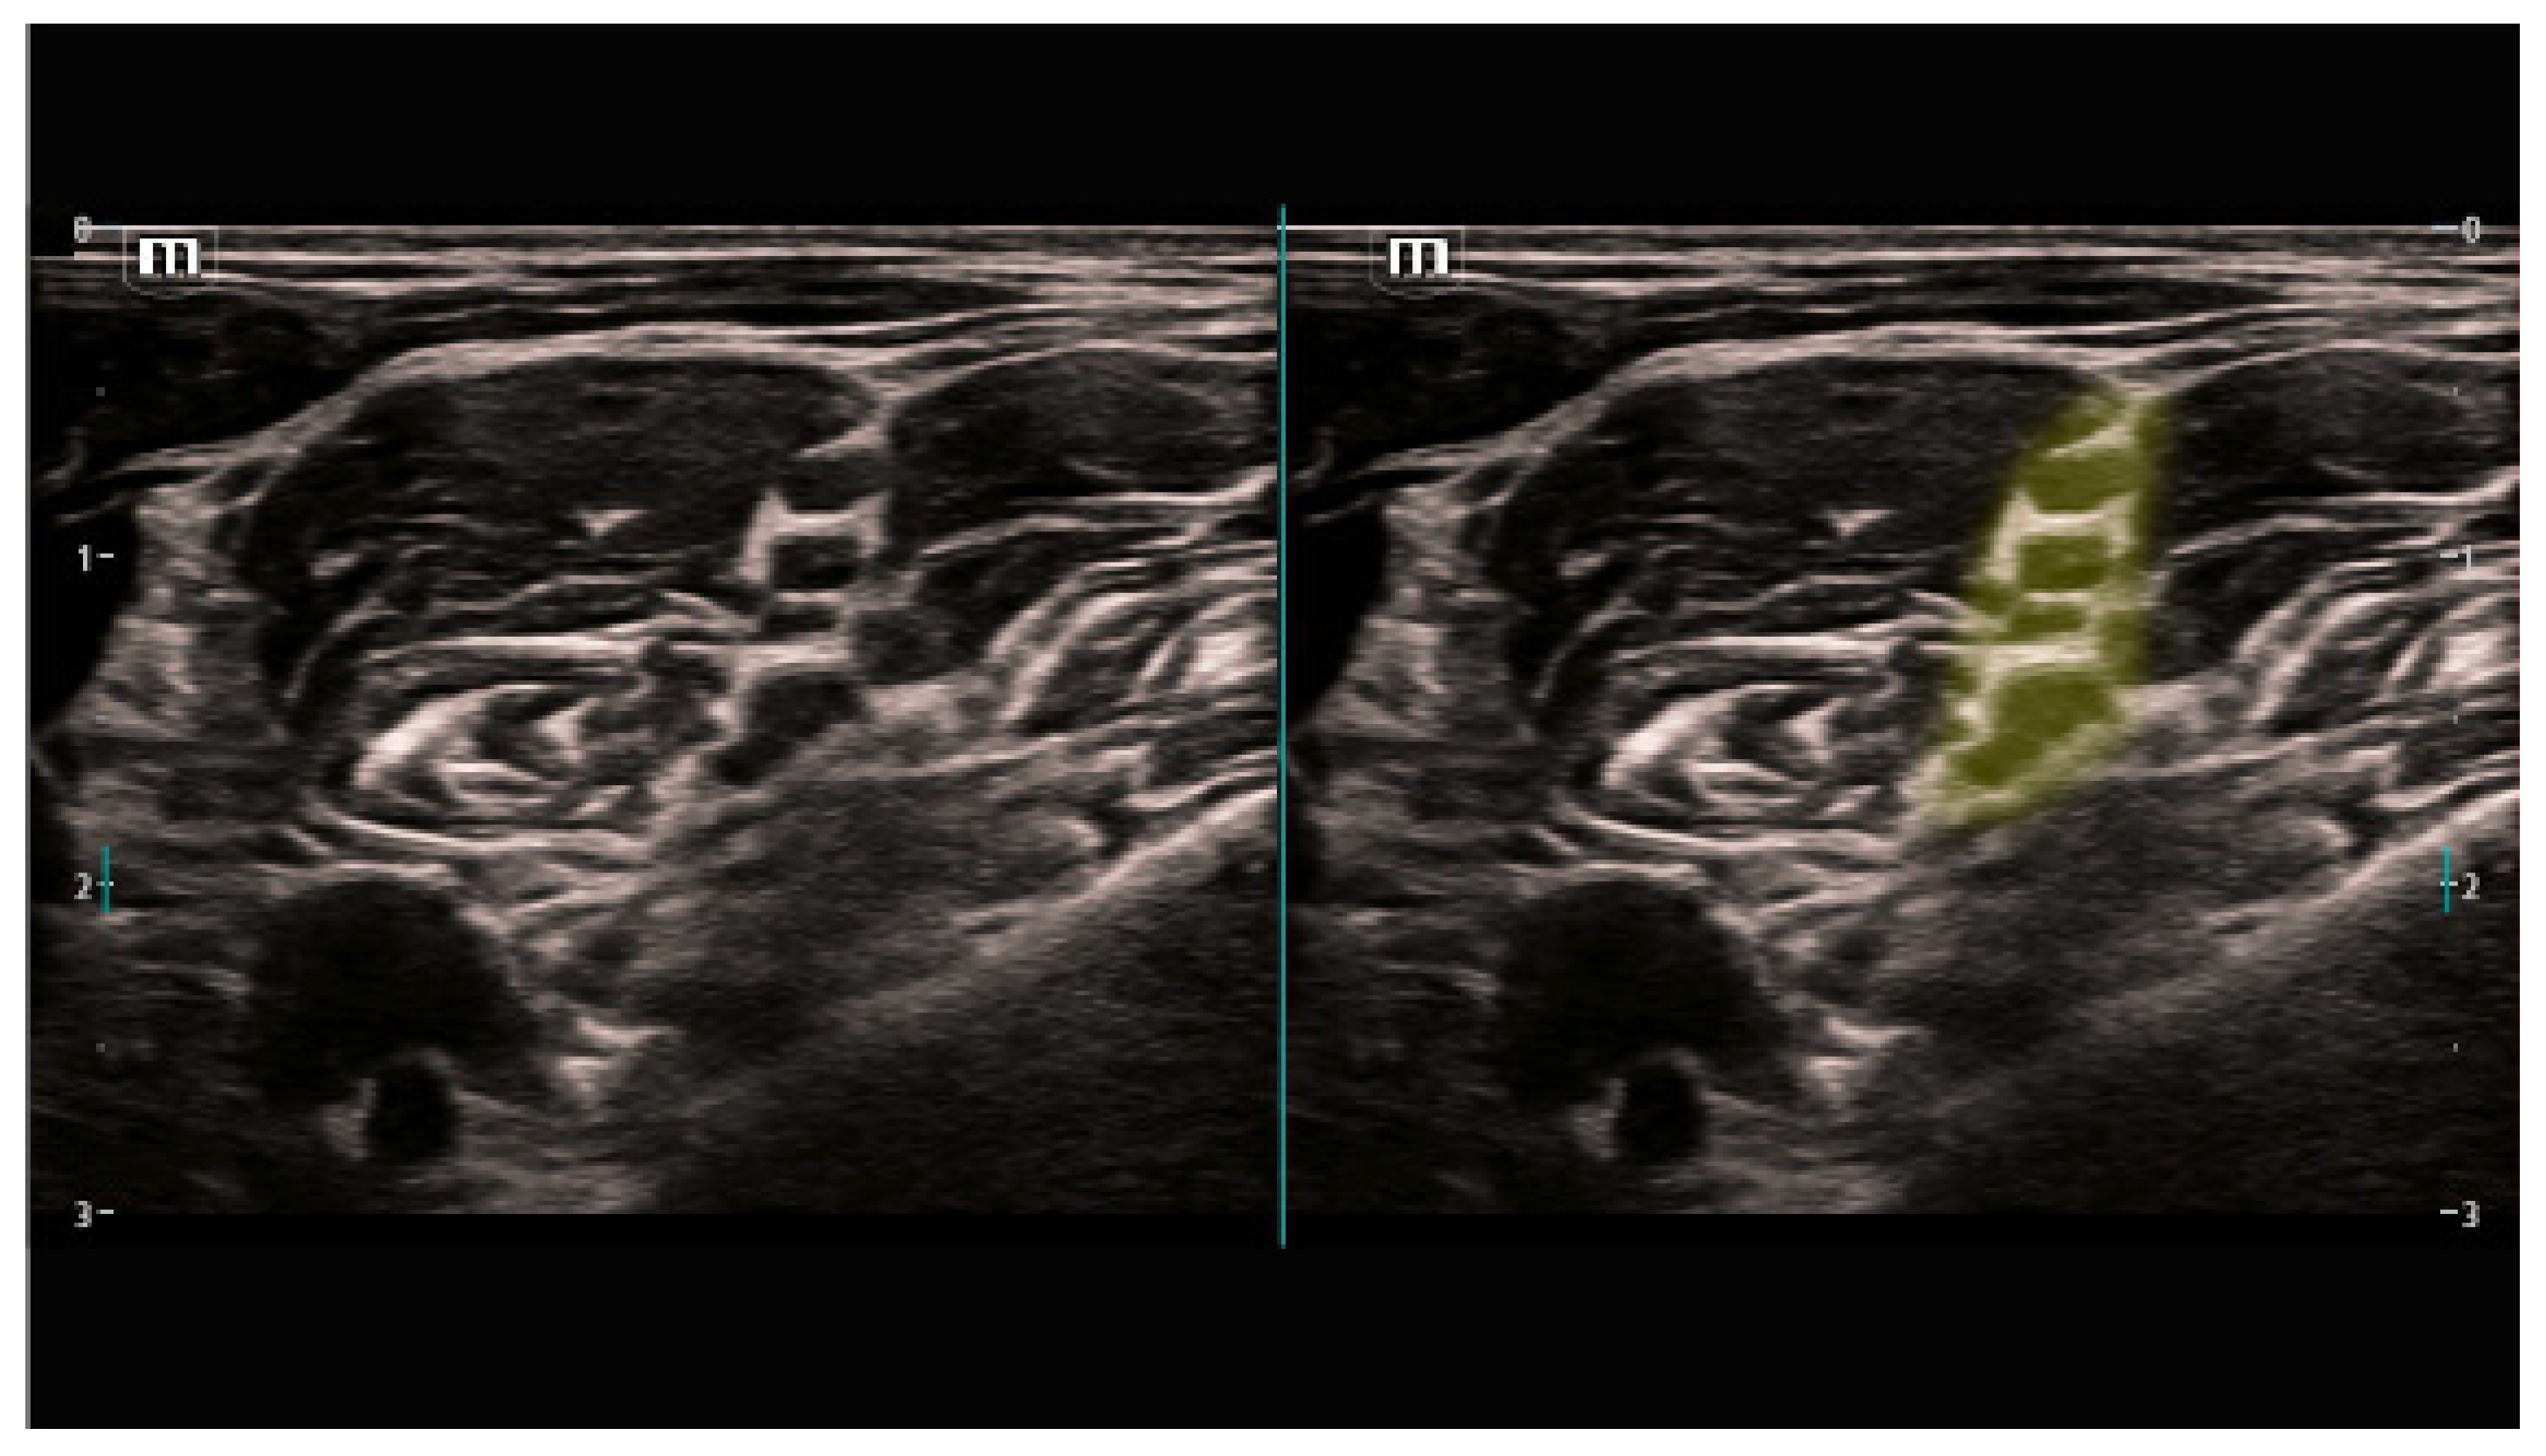

- Interscalene-level brachial plexus;

| Interscalene- Supraclaviular Level Brachial Plexus | ||

| Subclavian artery | 40/40 (100%) | 0/40 (0%) |

| Brachial plexus nerves | 40/40 (100%) | 0/40 (0%) |

| Sternocleidomastoid muscle | 40/40 (100%) | 0/40 (0%) |

| Scalenus anterior muscle | 40/40 (100%) | 0/40 (0%) |

| First rib | 40/40 (100%) | 0/40 (0%) |

| Pleura | 40/40 (100%) | 0/40 (0%) |

| Total (for block) | 240/240 (100%) | 0/240 (0%) |